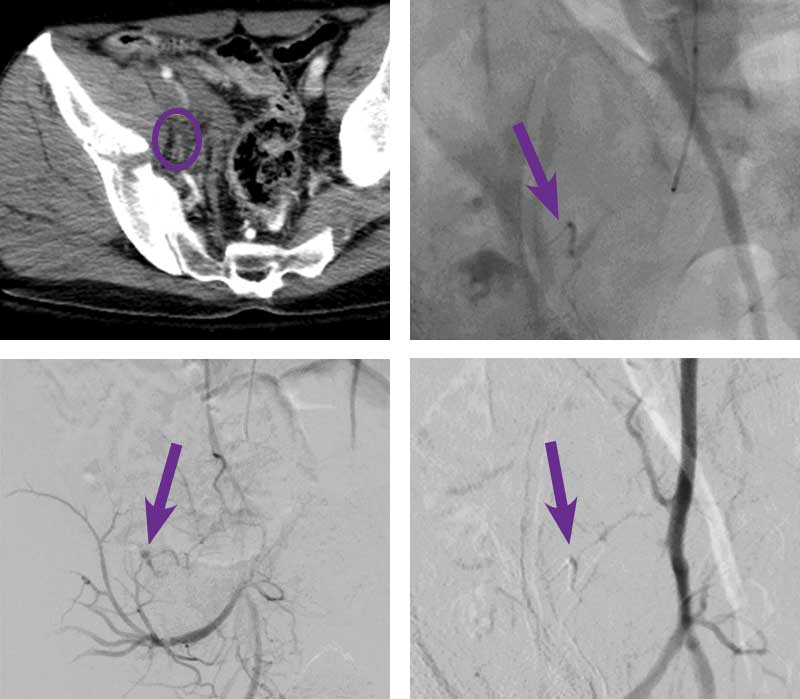

Right internal iliac artery embolization

Courtesy of Dr. Abhishek Kumar I Rutgers New Jersey Medical School

60-year-old man presented to a trauma center s/p two story fall. CT abdomen and pelvis revealed a complex right pelvic fracture with extraperitoneal hemorrhage and active extravasation (circle). Patient was started on a massive transfusion protocol and transferred to Interventional Radiology.

Intervention used

Left radial artery access was obtained and a 5 F sheath was placed. A 4 F angled catheter was used to select the right internal iliac artery. Angiography revealed active extravasation from a branch of the lateral sacral artery (red arrow). A 2.8 F microcatheter and 0.014” wire were used to catheterize the bleeding vessel. Embolization was performed with 0.2 cc of Obsidio Embolic using standard technique (purple arrow). Completion angiography from the internal iliac artery showed no further contrast extravasation.

Scan images from Obsidio right internal iliac artery embolization case.